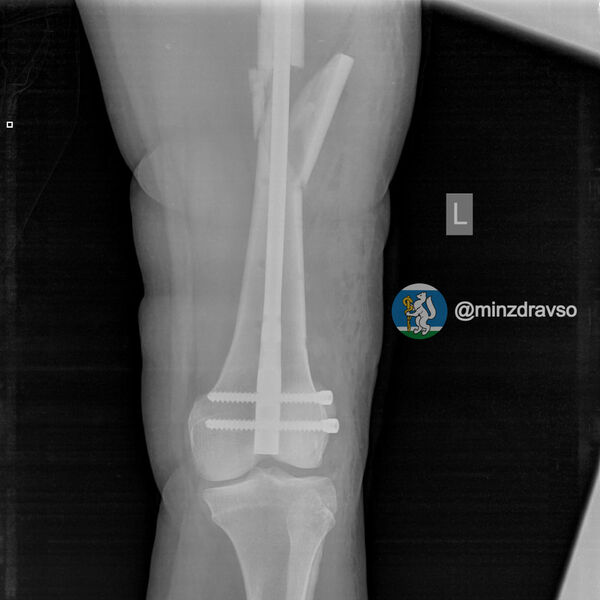

В Екатеринбурге 41-летняя беременная женщина упала с высоты десяти метров. В результате у нее диагностировали ушиб головы и сложный оскольчатый перелом левой бедренной кости, угрозы прерывания беременности медики не выявили.

Пациентке провели первую операцию в шоковой операционной приемного отделения. Через неделю, когда ее состояние стабилизировалось, женщине выполнили вторую операцию по замене аппаратов внешней фиксации на внутренний фиксатор. Для дальнейшего ведения беременности ее перевели в другую больницу.